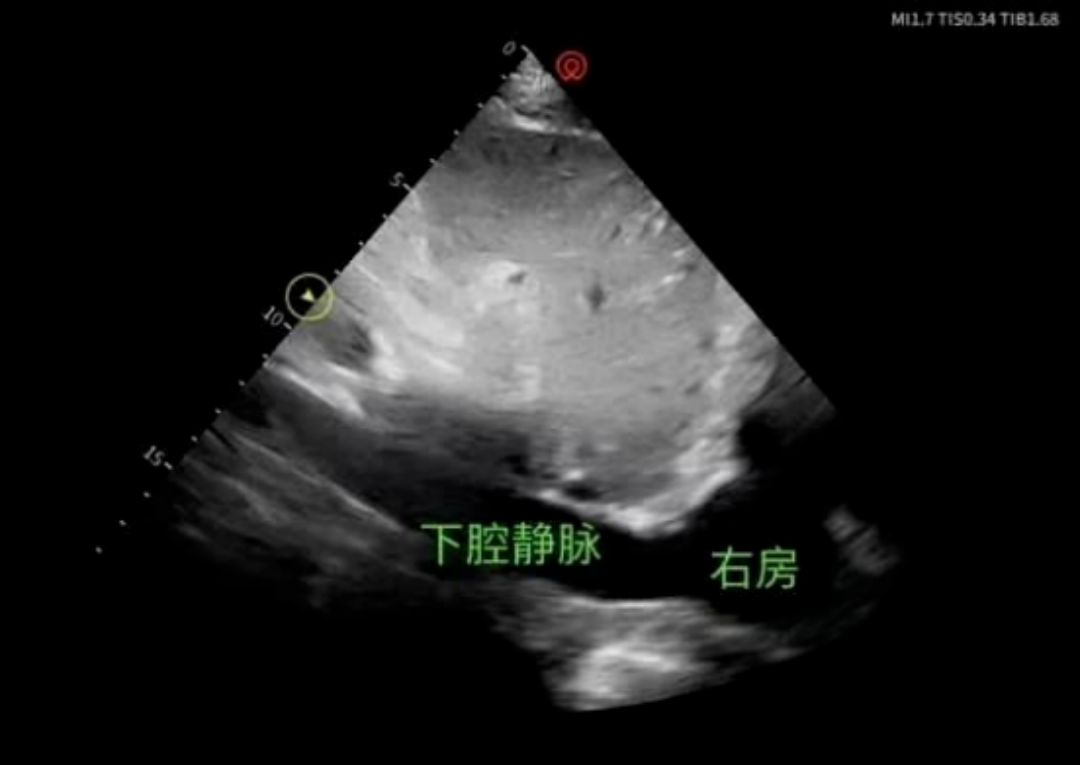

教学现场,刘芝艳教授围绕床旁下腔静脉超声评估的核心要点展开细致带教,逐一进行示范讲解,针对性纠正操作细节,帮助团队牢牢掌握技术精髓。科室医生严格遵循操作规范,精准定位下腔静脉各测量节段,实时捕捉血管动态影像,细致记录相关数据,认真学习操作流程、指标判读等核心内容,积极交流答疑,切实将理论知识与临床实操相结合。

相较于传统依靠经验判断容量的方式,床旁超声下腔静脉评估技术具备无创、便捷、可动态重复、无需转运患者等优势,有效避免了盲目补液引发的肺水肿、心衰等并发症,实现了从“经验诊疗”向“精准可视化诊疗”的转变,为休克、脓毒症、术后危重等各类患者的液体复苏、循环支持提供了强有力的技术支撑,大幅提升了危重症患者救治的安全性与有效性。